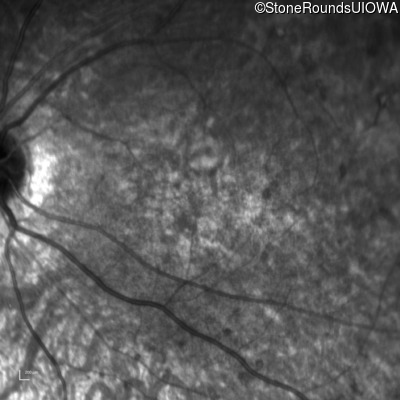

Infrared Fundus Photograph - Left - 5/200

Exemplar